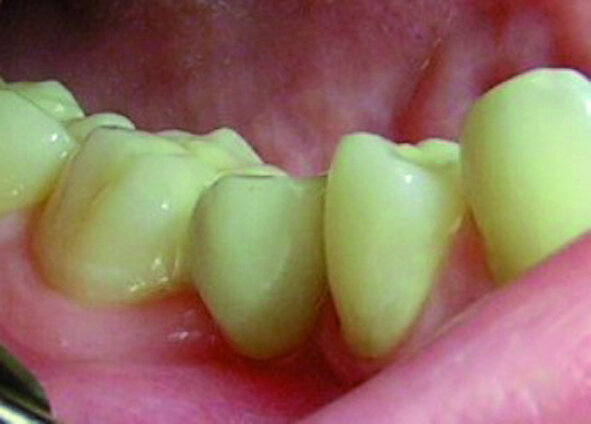

Les deuxièmes prémolaires peuvent être résumées par les mots « je veux créer » ou « mon moi créatif » (Fig. 3). La deuxième prémolaire supérieure droite symbolise ce que l’on veut développer dans le monde extérieur, nos enfants ou nos hobbies, et la deuxième prémolaire supérieure gauche nos dons naturels. La deuxième prémolaire inférieure droite, similairement à la première prémolaire adjacente, témoigne de notre capacité d’accomplir nos projets, particulièrement dans le domaine du travail. Ainsi, après la restauration d’une anodontie au moyen d’un bridge sur inlay, une jeune patiente dans l’indécision a terminé brillamment ses études au grand bonheur de ses parents (Fig. 4). Par contre les figures 5 et 6 sont des photographies de patients chez qui l’évolution professionnelle se place toujours au second rang des priorités.